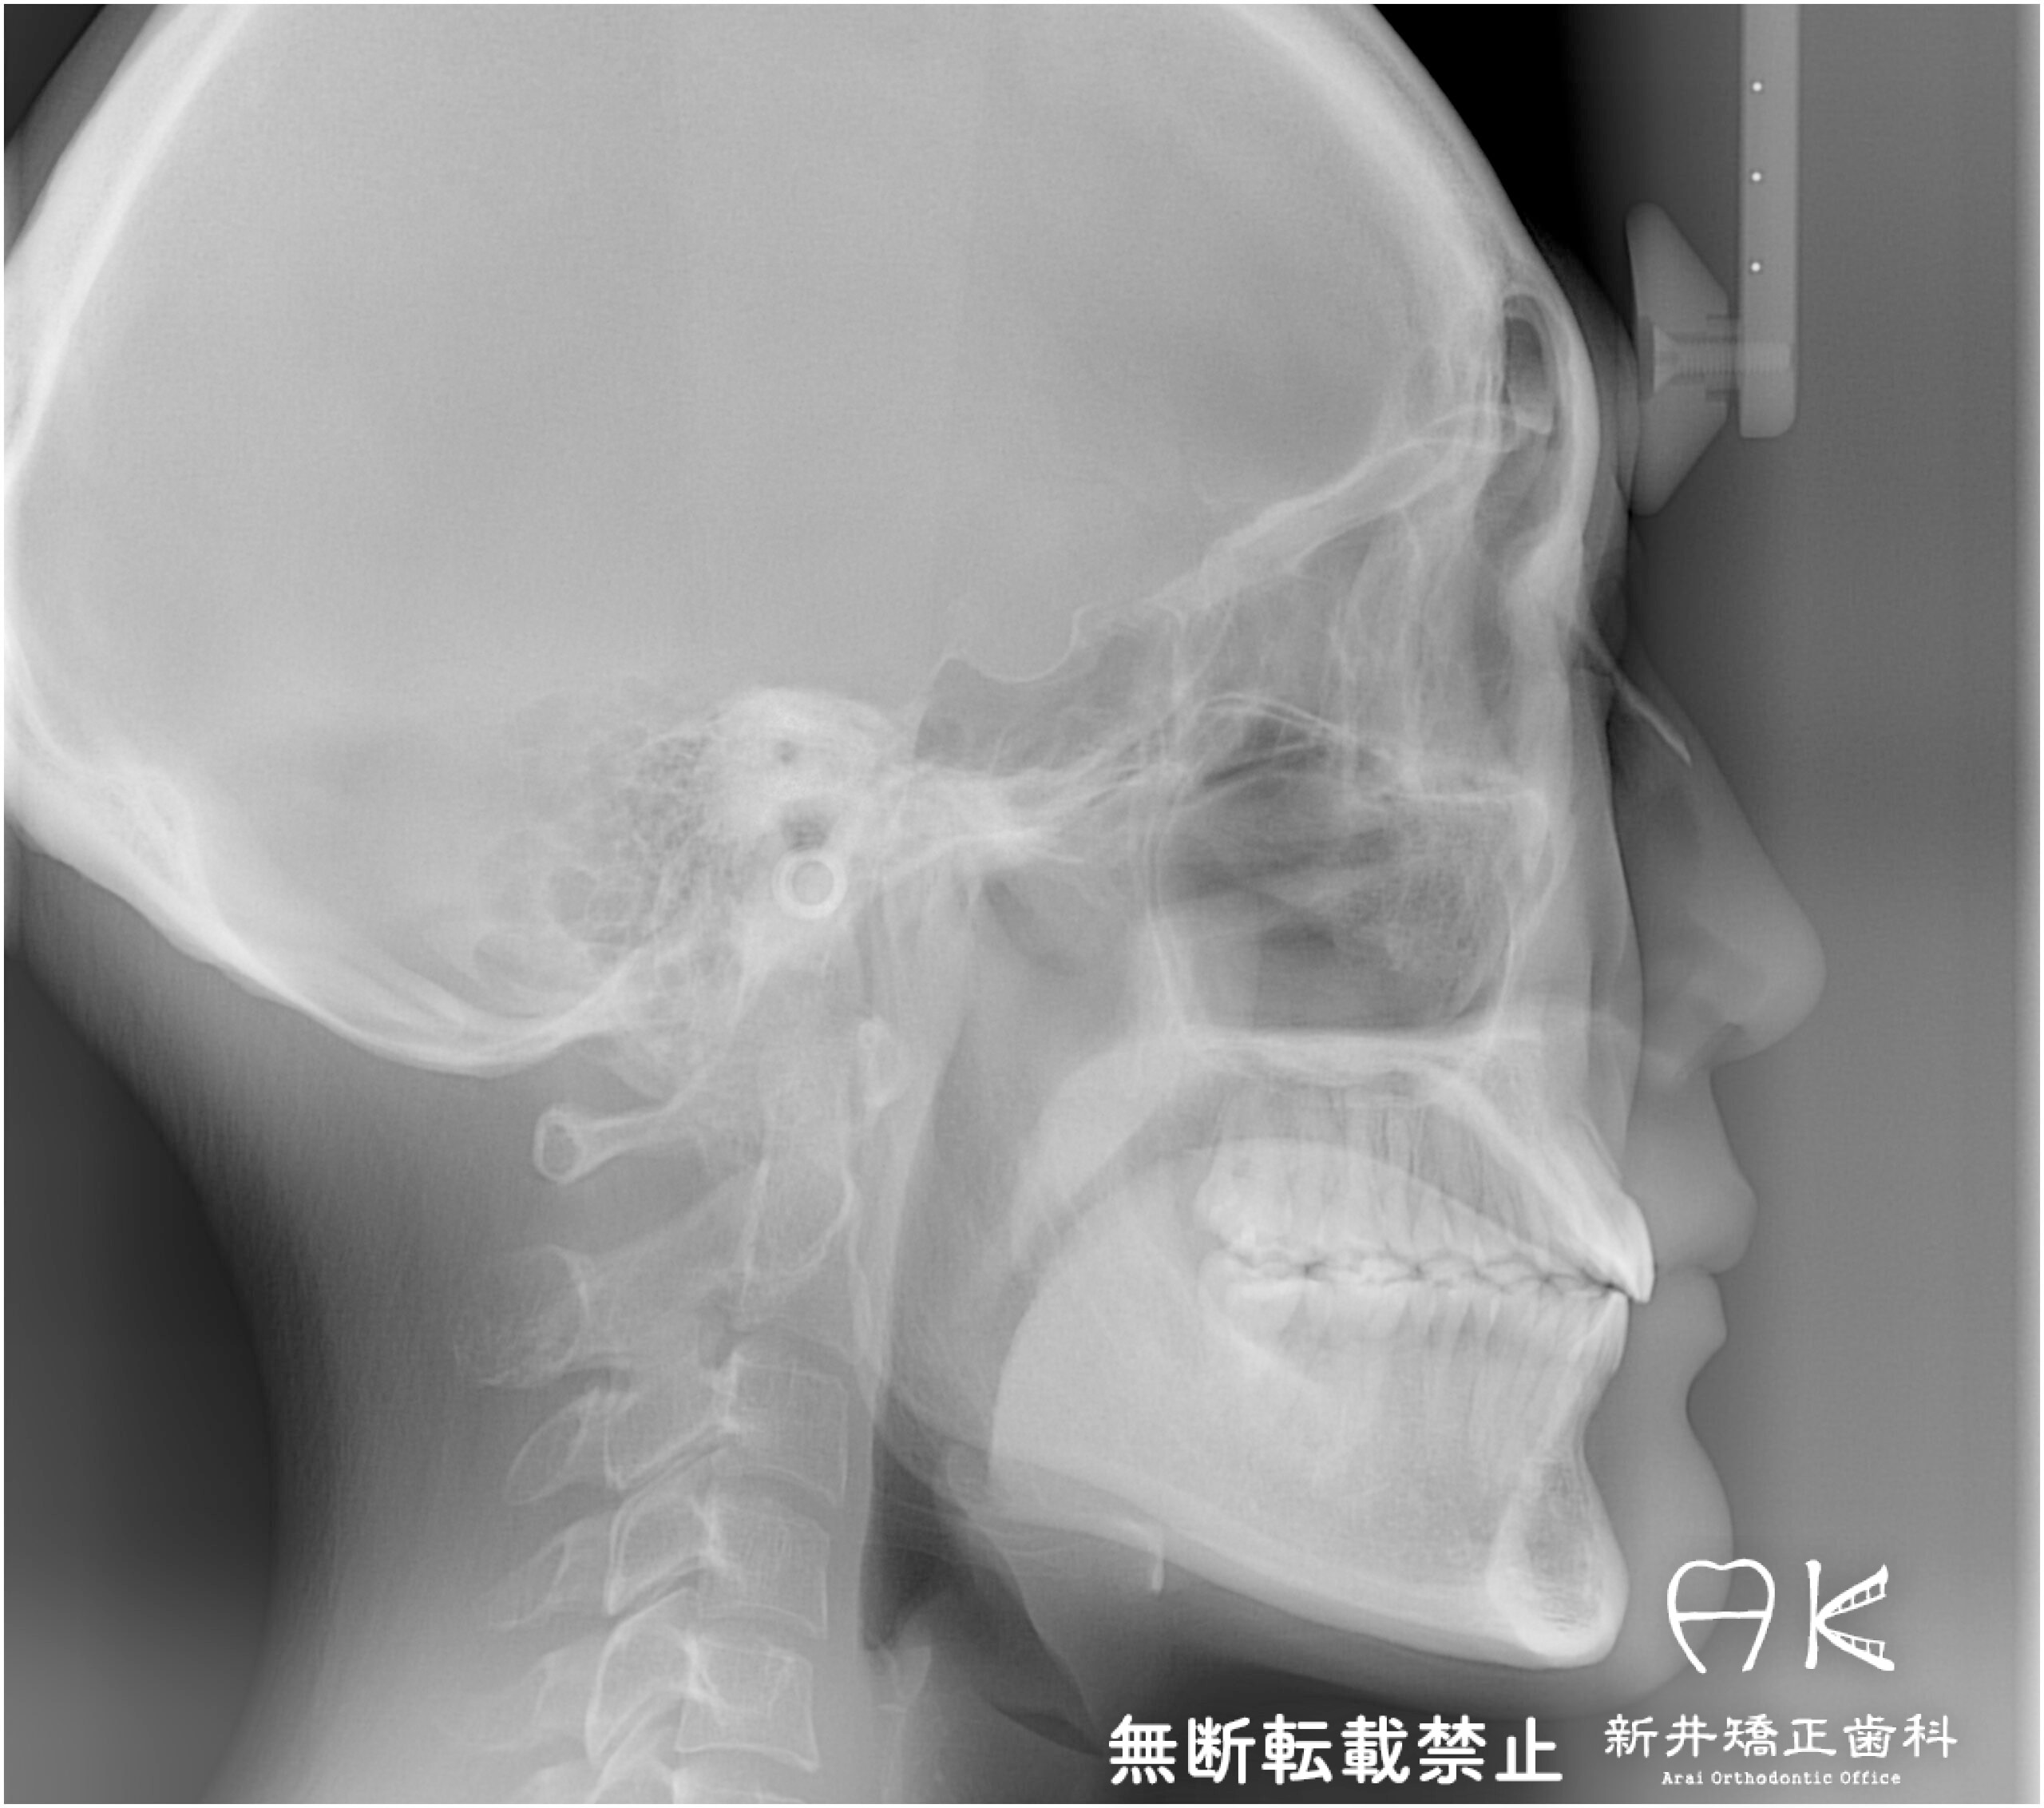

セファログラムのトレースの重ね合わせ(緑:治療前、赤:治療終了時)

| 治療前 | 上顎右側側切歯(2番目の歯)、上顎両側第二小臼歯(5番目の歯)、下顎右側中切歯(1番目の歯)、下顎左側第一大臼歯(6番目の歯)の合計5本の歯が先天的に欠損していた患者さんです。 先天欠損の他にも下顎骨の後退による骨格的な出っ歯の症状もありました。 矯正治療を開始する際に左上と左下のブリッジを切断し、上顎は隙間を全て閉じます。下顎左側第一大臼歯相当部はすでに歯槽骨が細くなっていたため、スペースを残して治療を進めていくこととしました。 |

| 治療後 | 前歯から奥歯まで全体的に緊密な咬み合わせになっています。 治療前はブリッジがあったため歯を抜いたように見えますが、元々歯の本数が少ないため、歯を抜くことなく現存する歯でかみ合わせを作りました。 出っ歯でもあり口元の突出感もありましたが、すっきりとした綺麗なイーラインになりました。 嚙むという機能性と見た目の審美性、どちらも患者さんにとって満足いく結果となりました。 |